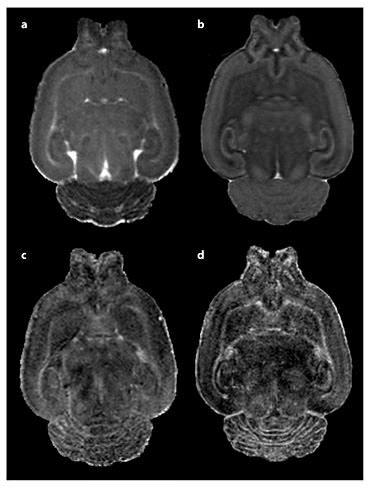

One of the main concerns in imaging sequence design is whether the animal will be scanned in vivo or postmortem. While live imaging is more attractive from both a translational point of view and the possibility of longitudinal studies [90,91,92,93], it has several limitations. Since the animal has to be anesthetized during image acquisition, the scan has to be relatively short, typically less than 3–4 h for an appropriate resolution. This leads to reduced resolution, decreased SNR, fewer gradient directions, or a combination of these, as shown in figure 4. Depending on the nature of the study, there might be additional concerns regarding the effect of the anesthesia on both long- and short-term development [81], as well as the strain placed on the animal during the whole process. In our own work, we have had considerable trouble keeping animals, especially young pups, alive while maintaining a high enough anesthesia dose to prevent motion artifacts for a long enough scan time to ensure adequate SNR. While an extensive review of MRI contrast agents is beyond the scope of this paper [see [94]], it is noteworthy that postmortem imaging may allow for the use of contrast agents such as Prohance to increase SNR; however, some of these agents may not be appropriate to use with live developing animals or humans due to their toxicity and concerns about their retention levels in blood as well as in the kidneys and lungs [95,96].

MD (a, b) and fractional anisotropy (c, d) images of a PND 14 Sprague-Dawley rat pup brain. Following in vivo image collection shown in a and c, the subject was perfused, decapitated, and whole head reimaged ex vivo shown in b and d. In vivo scanning was accomplished under isoflurane anesthesia in our Bruker 9.4-tesla MRI. A 3D RARE sequence was used with diffusion gradients applied in six noncollinear directions. Total scan time of approximately 2.5 h, resulting in a resolution of 0.15 × 0.16 × 0.17 mm. Ex vivo imaging was accomplished overnight via another RARE DTI scan protocol with 21 diffusion direction images at an isotropic voxel size of 0.12 × 0.12 × 0.12 mm. The total scan time was approximately 15.5 h. By comparing these two images, we can see both the greater resolution and SNR of the fixed brain images, which came at the cost of reduced translational relevancy and the sacrifice of a longitudinal study design.

MD (a, b) and fractional anisotropy (c, d) images of a PND 14 Sprague-Dawley rat pup brain. Following in vivo image collection shown in a and c, the subject was perfused, decapitated, and whole head reimaged ex vivo shown in b and d. In vivo scanning was accomplished under isoflurane anesthesia in our Bruker 9.4-tesla MRI. A 3D RARE sequence was used with diffusion gradients applied in six noncollinear directions. Total scan time of approximately 2.5 h, resulting in a resolution of 0.15 × 0.16 × 0.17 mm. Ex vivo imaging was accomplished overnight via another RARE DTI scan protocol with 21 diffusion direction images at an isotropic voxel size of 0.12 × 0.12 × 0.12 mm. The total scan time was approximately 15.5 h. By comparing these two images, we can see both the greater resolution and SNR of the fixed brain images, which came at the cost of reduced translational relevancy and the sacrifice of a longitudinal study design.